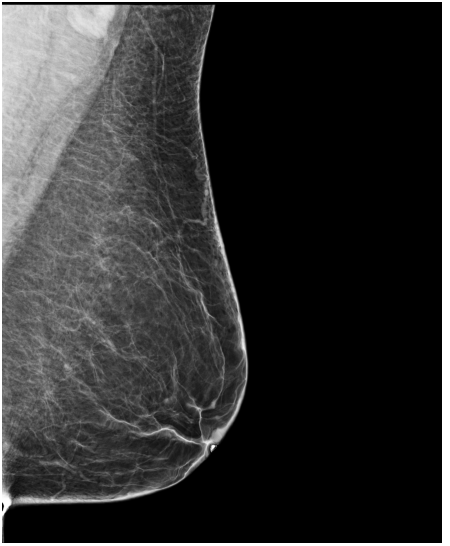

4.3 Pre-processing

The EMBED and CSAW-CC datasets originally consist of images in DICOM format, which are converted into 16-bit grayscale PNG images for consistency and compatibility. Following the pre-processing procedure outlined in (Yala et al.,, 2021), we enhanced image quality and removed background artifacts—such as textual annotations commonly present in mammography images—by applying a contour detection procedure. All contours in the image are detected, and only the largest contour, corresponding to the breast tissue, is retained. This contour is then used to create a mask that isolates the breast region from the background. The isolated breast image is resized to a size of 1664×20481664\times 2048 pixels while preserving the aspect ratio. Finally, the resized image is normalized and converted to a 16-bit format.

Following (Wang et al.,, 2024), we included only patients with at least five years of follow-up data for risk prediction. The datasets are randomly split at the patient level into training, validation, and test sets in a 5:2:3 ratio. Table1 presents the distribution of the Time-to-Cancer label and the dataset split for both the EMBED and CSAW-CC datasets.